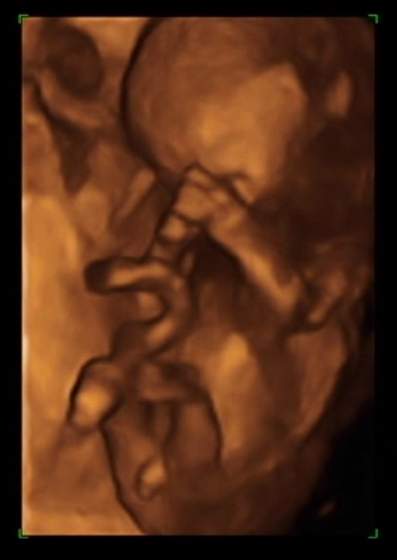

Goga no właśnie ciekawe, tym bardziej, że tak niby w dół a jednocześnie spore haha, a powiedz to było jakieś 3d? mega fajowe zdjęcie!

a USG było 3D